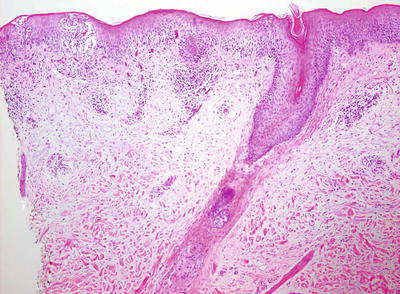

Histologic changes in acute atopic dermatitis are quite subtle. Scant wispy parakeratosis overlies an epidermis that demonstrates slight spongiosis and small collections of Langerhans cells [3] (Fig. 1.2). Scattered eosinophils may be present in the superficial dermis, admixed with increased numbers of lymphocytes [4] (Fig. 1.3). Degranulated mast cells may be present but are rarely observed on routine histologic sections. A folliculocentric pattern with spongiosis concentrated within follicular infundibula has been described, and is more common in darker skinned individuals [5].

Fig. 1.2

Atopic dermatitis presents with a mild spongiotic dermatitis and a mild lymphocytic infiltrate in the superficial dermis